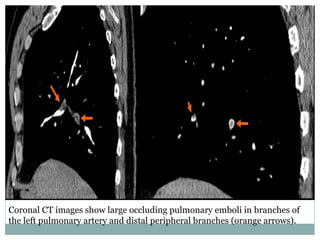

Coronal CT images show large occluding pulmonary emboli in branches of

the left pulmonary artery and distal peripheral branches (orange arrows).